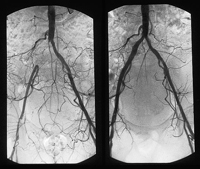

Endovascular surgery endeavors, by means of catheters, to resolve problems of little access or narrowing of blood vessels, above all, aneurysms or stenosis, in particular, iliac or aortoiliac.

Endovascular surgery resolves many cases of vascular illness (stenosis, occlusions, aneurysms, fistulas….) with a simple percutaneous approach. By means of the introductions of guides and catheters through a vessel, normally the femoral artery, which serves to transport by dilatation balloons, the endograft. The patient benefits from the advantages of local anesthesia, a less aggressive technique and a shorter and more comfortable post-operative recuperation; in many cases it can be performed one day in the hospital, with an admission of 24 hours.

Among the most commonly utilized methods stand out Angioplasty and endografts.